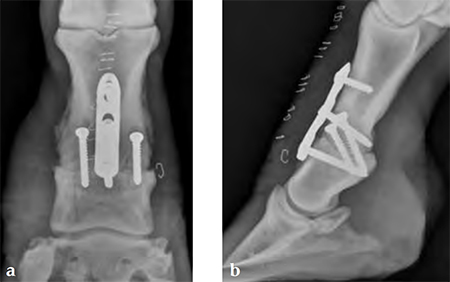

Compression across the joint was achieved by placing the abaxial transarticular 5.5 mm cortical screws in lag fashion, then using the cortex screw in the load position of the proximal combination hole. The screws on either side of the joint are 5.0 mm locking screwsthe most distal screw is placed first, then the cortex screw is used to provide dynamic compression and the final locking screw is placed.

Compared to the standard locked plate design the toenail design at one end of the plate was eliminated and the most distal hole changed from a combination hole to a stacked combination hole. These changes allow the plate to be placed as close to the joint as possible. The two proximal combination holes face the same way (to achieve compression across the joint) and the gap between the stacked combination hole and the first combination hole was lengthened so that it matches the 4.5 mm narrow DCP (to span the joint).